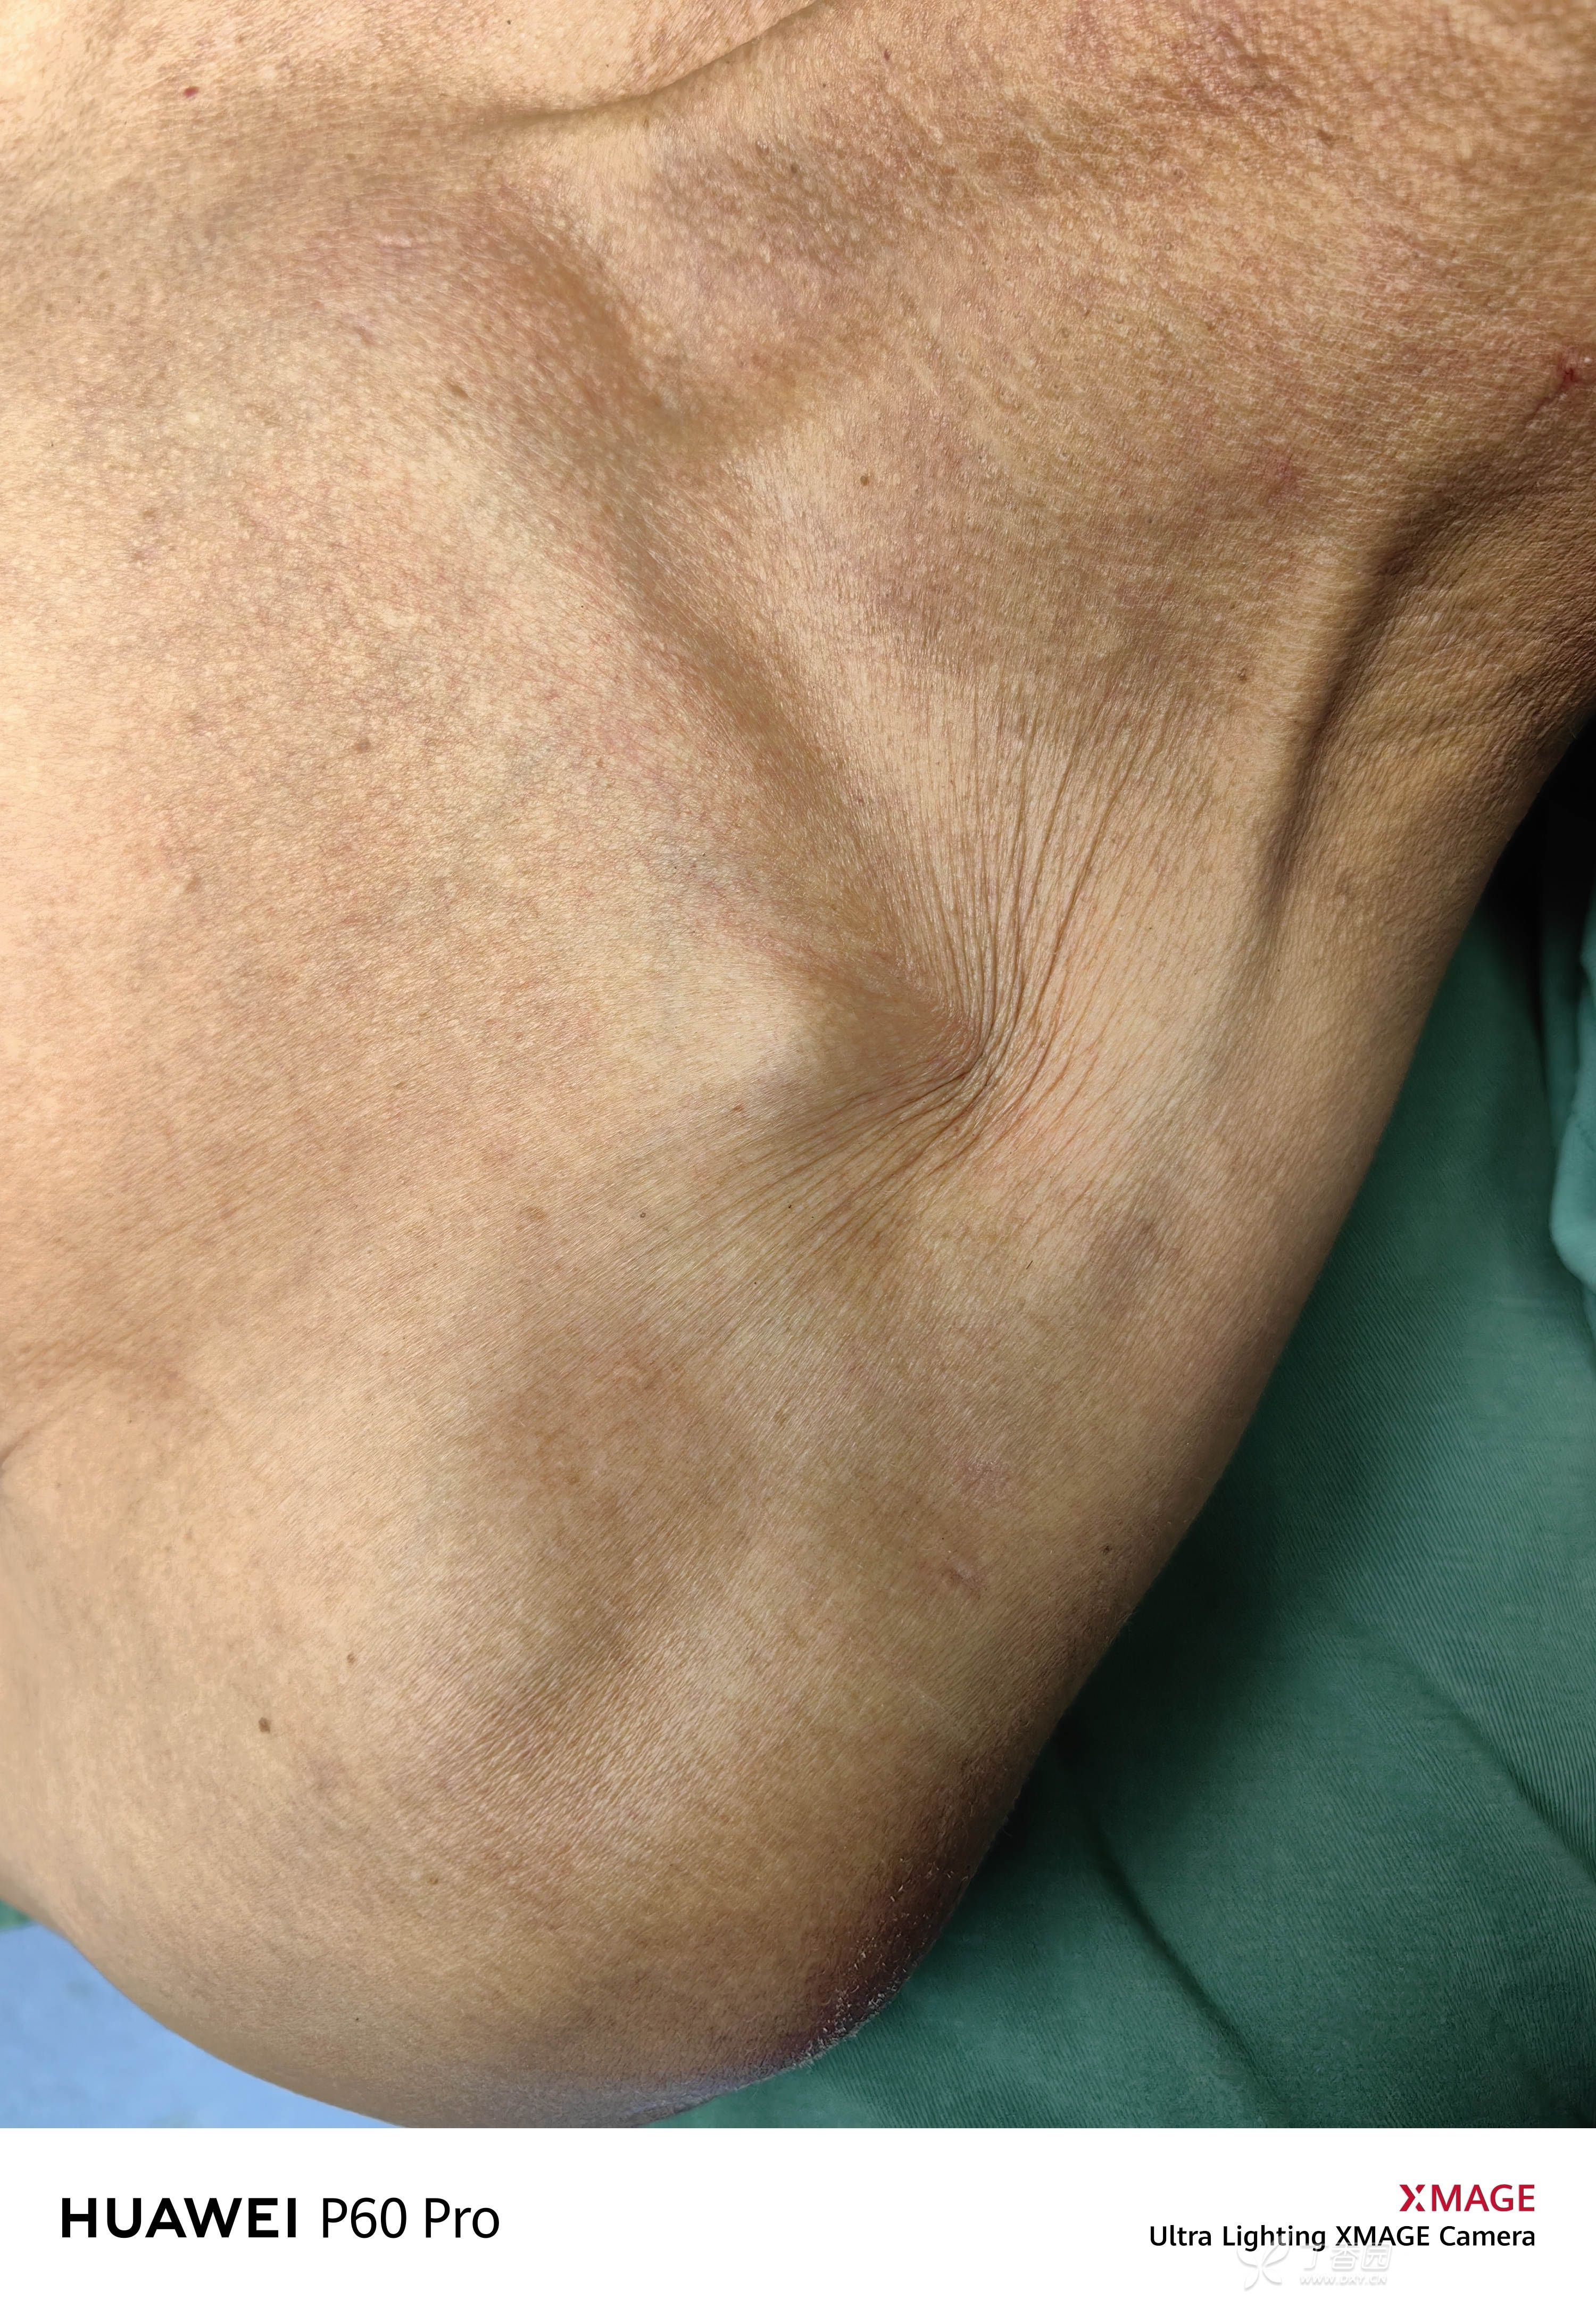

外观:可见橘皮征,骨折端卡压软组织